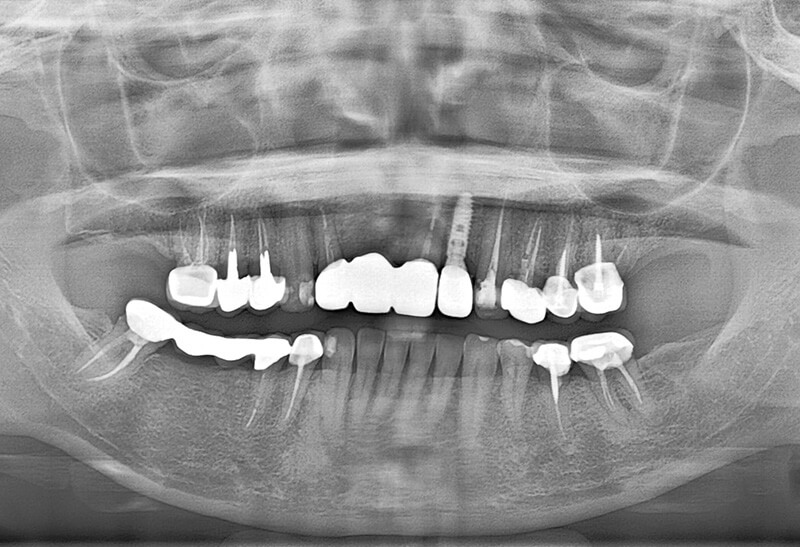

拯救他院植牙案例